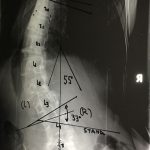

Εικ. 2 Προ-εγχειρητικός ακτινολογικός έλεγχος. Παρατηρείται η ύπαρξη αριστερού θωρακο-οσφυϊκού κυρτώματος (Θ10 – Ο3) 55 μοιρών.